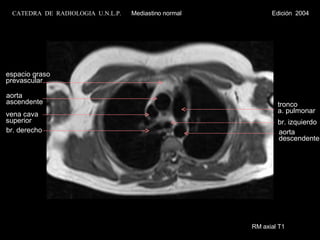

RM axial T1 aorta ascendente vena cava superior br. derecho tronco  a. pulmonar espacio graso prevascular br. izquierdo aorta descendente CATEDRA  DE  RADIOLOGIA  U.N.L.P.   Mediastino normal  Edición  2004

RM axial T1aorta ascendente vena cava superior br. derecho tronco a. pulmonar espacio graso prevascular br. izquierdo aorta descendente CATEDRA DE RADIOLOGIA U.N.L.P. Mediastino normal Edición 2004